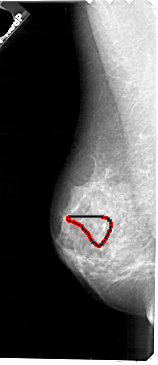

A_1723_1.RIGHT_MLO

LEFT_MLO LINES 5461 PIXELS_PER_LINE 2356 BITS_PER_PIXEL 12 RESOLUTION 43.5 OVERLAY

FILE: A_1723_1.LEFT_MLO.OVERLAY

TOTAL_ABNORMALITIES 1

ABNORMALITY 1

LESION_TYPE CALCIFICATION TYPE PLEOMORPHIC DISTRIBUTION SEGMENTAL

ASSESSMENT 4

SUBTLETY 3

PATHOLOGY MALIGNANT

TOTAL_OUTLINES 1

BOUNDARY